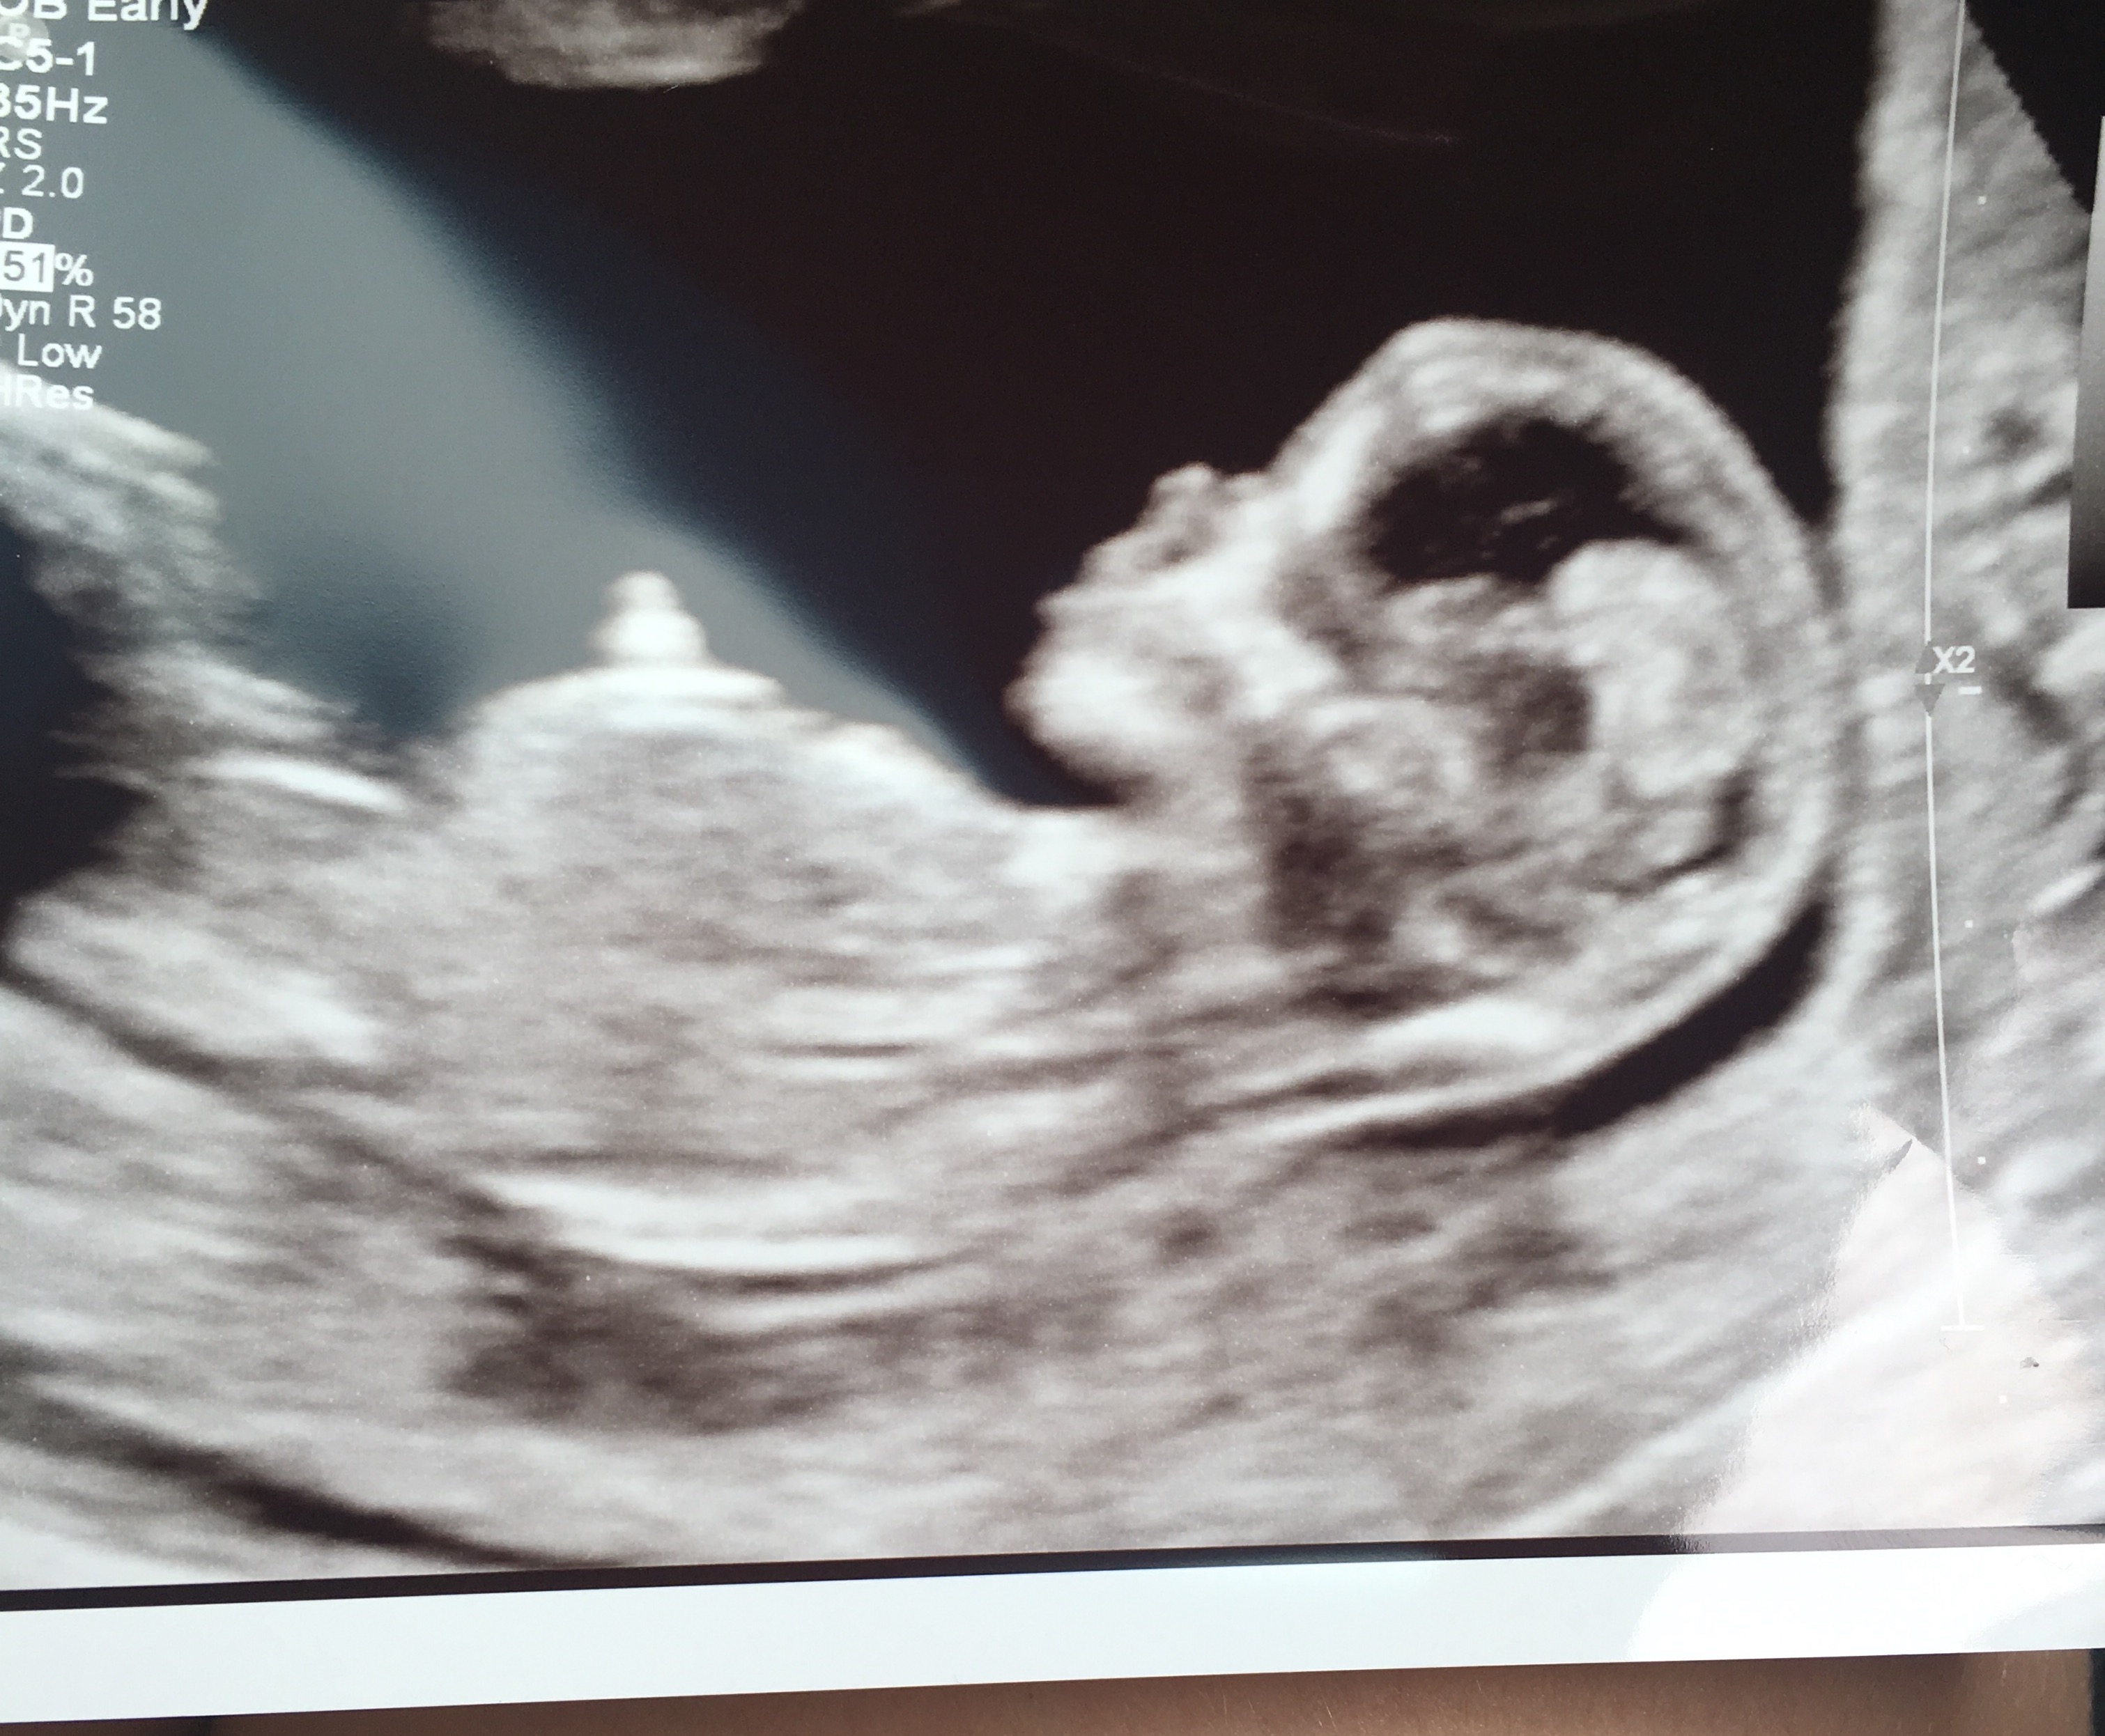

Attachment 3228813 1/2 weeks! Attachment 32289Attachment 32290